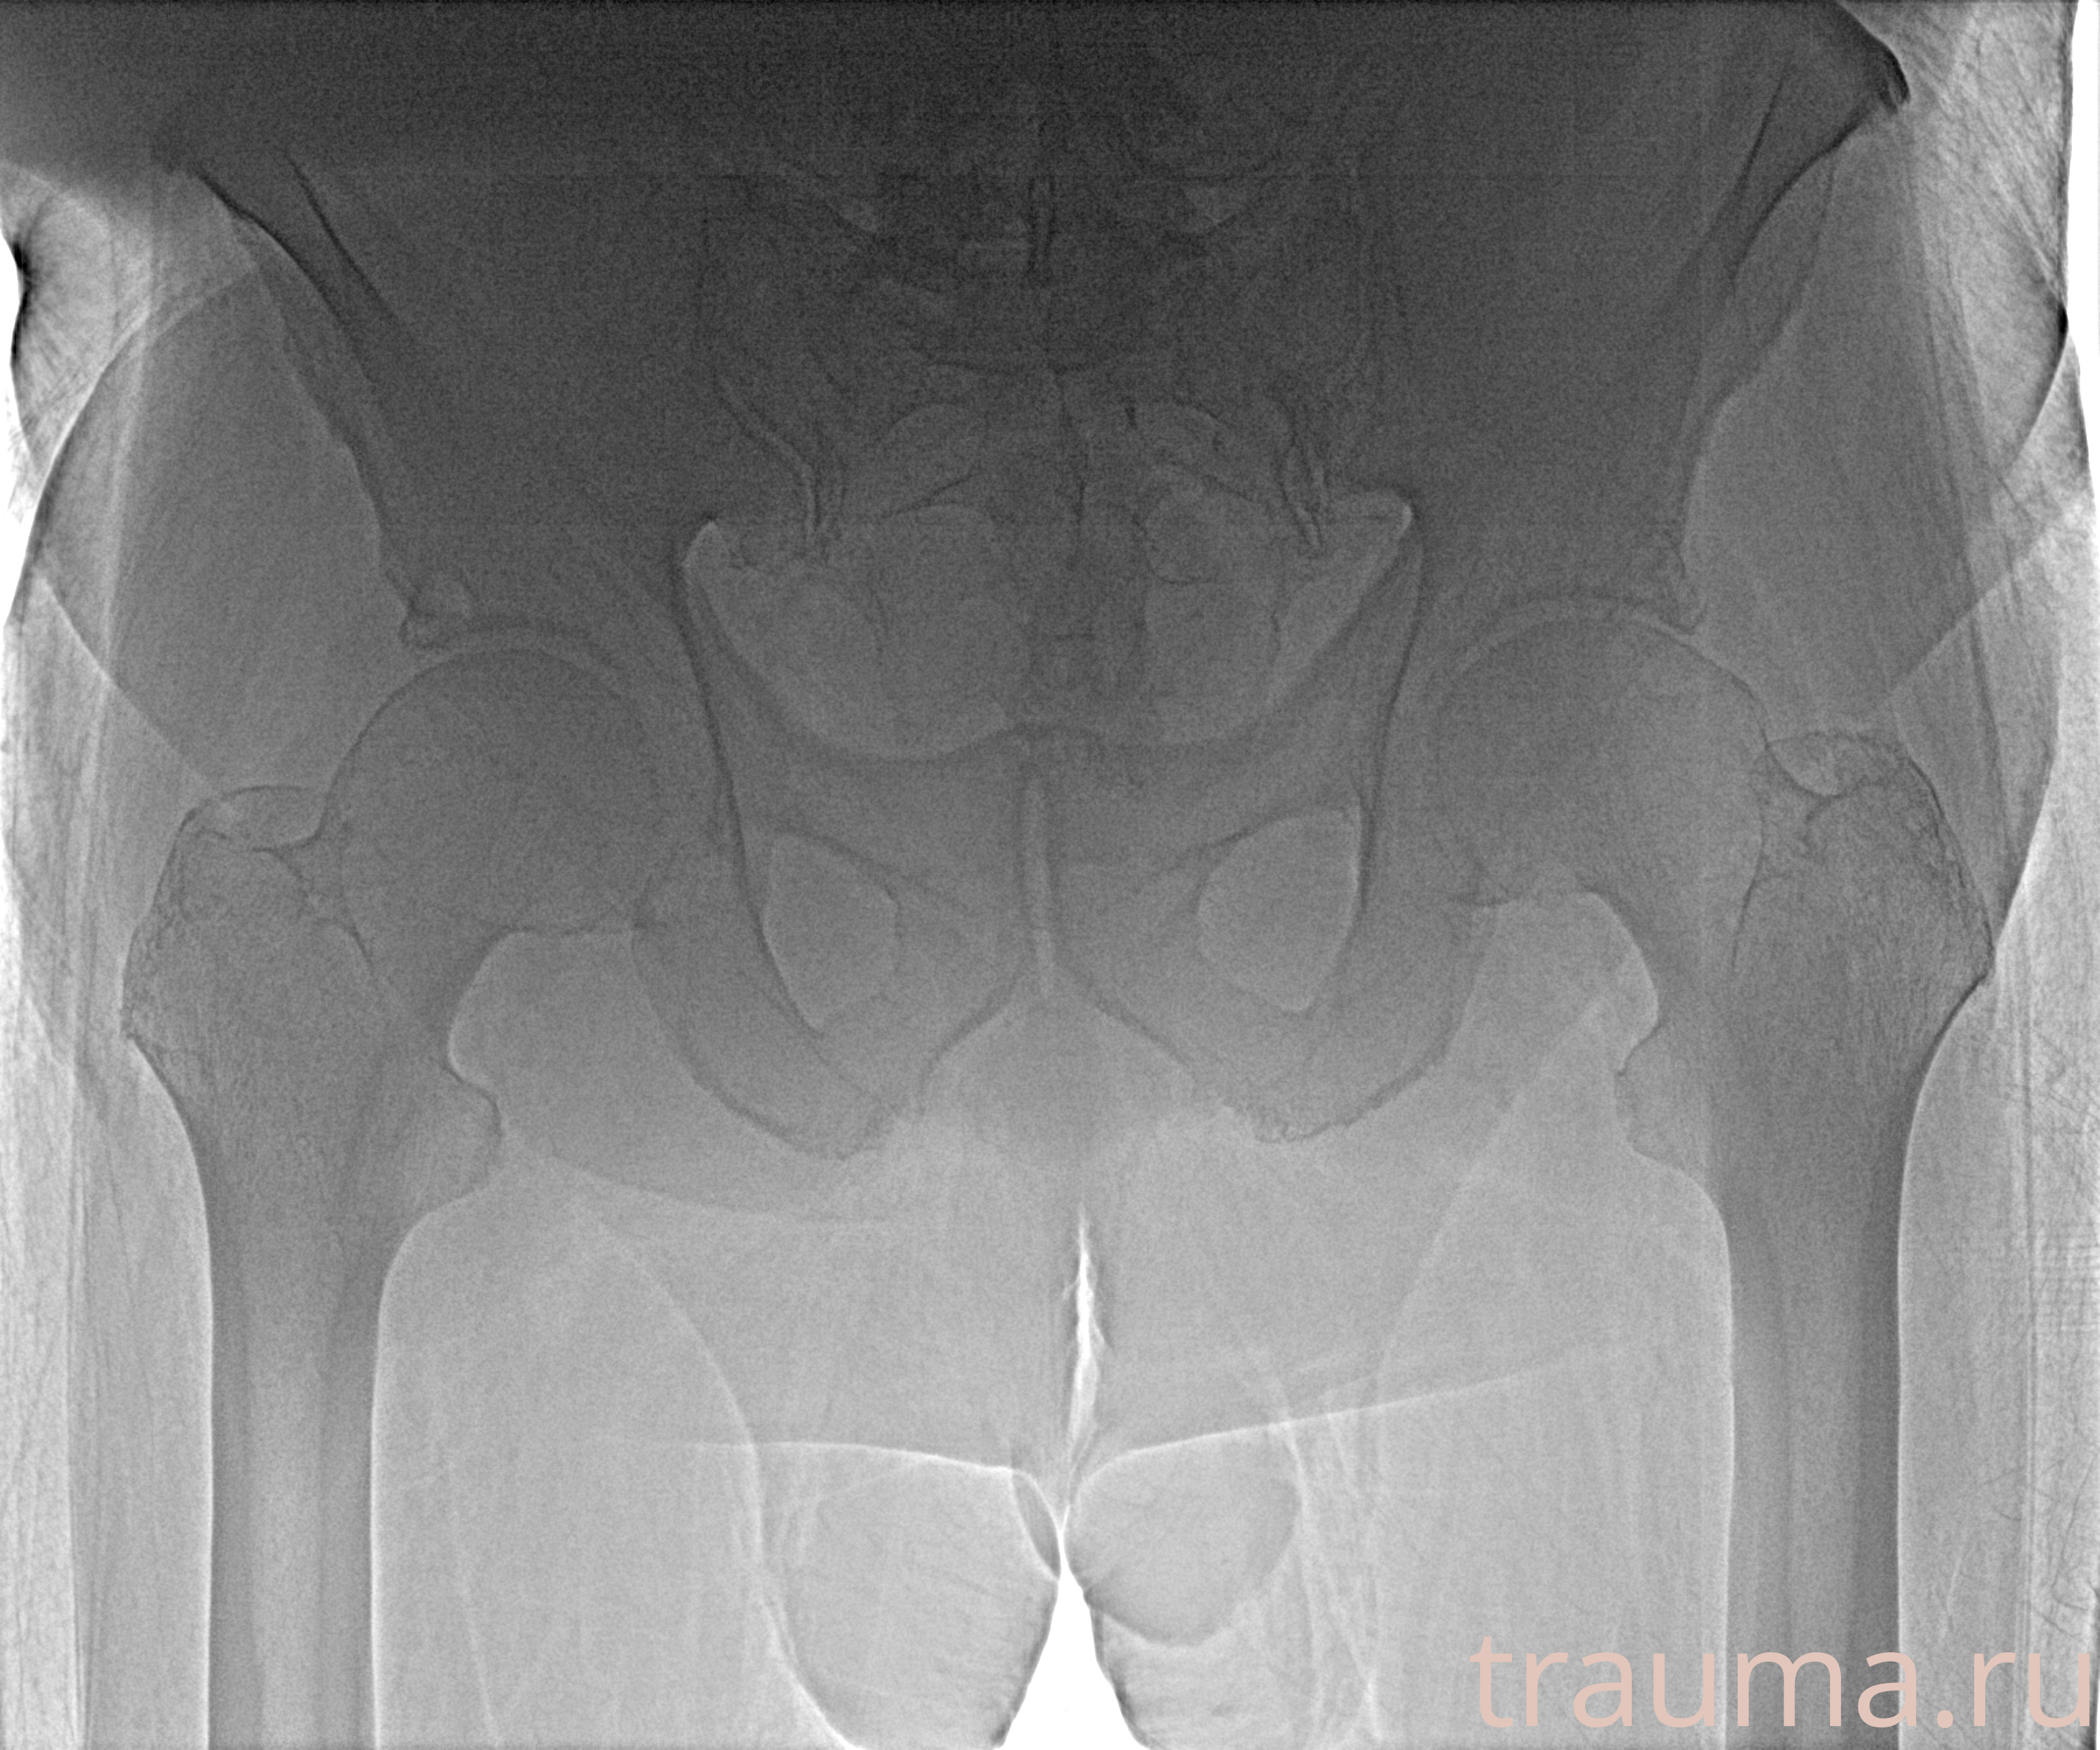

Рентген на дому: по вашему адресу приезжает врач-рентгенолог, травматолог-ортопед с мобильным рентгеновским аппаратом, проводит диагностику травмы или заболевания, делает необходимые рентгенограммы, дает рекомендации по дальнейшему лечению. Получить качественные снимки в домашних условиях возможно благодаря уникальной методике, разработанной МосРентген Центром для института  Склифосовского